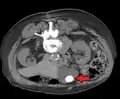

Diagnosis

Diagnosis is typically confirmed by abdominal ultrasound. Other imaging techniques used are ERCP and MRCP. Gallstone complications may be detected on blood tests.[2]